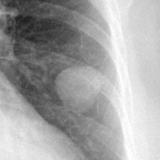

Hamartoma 1 Lat